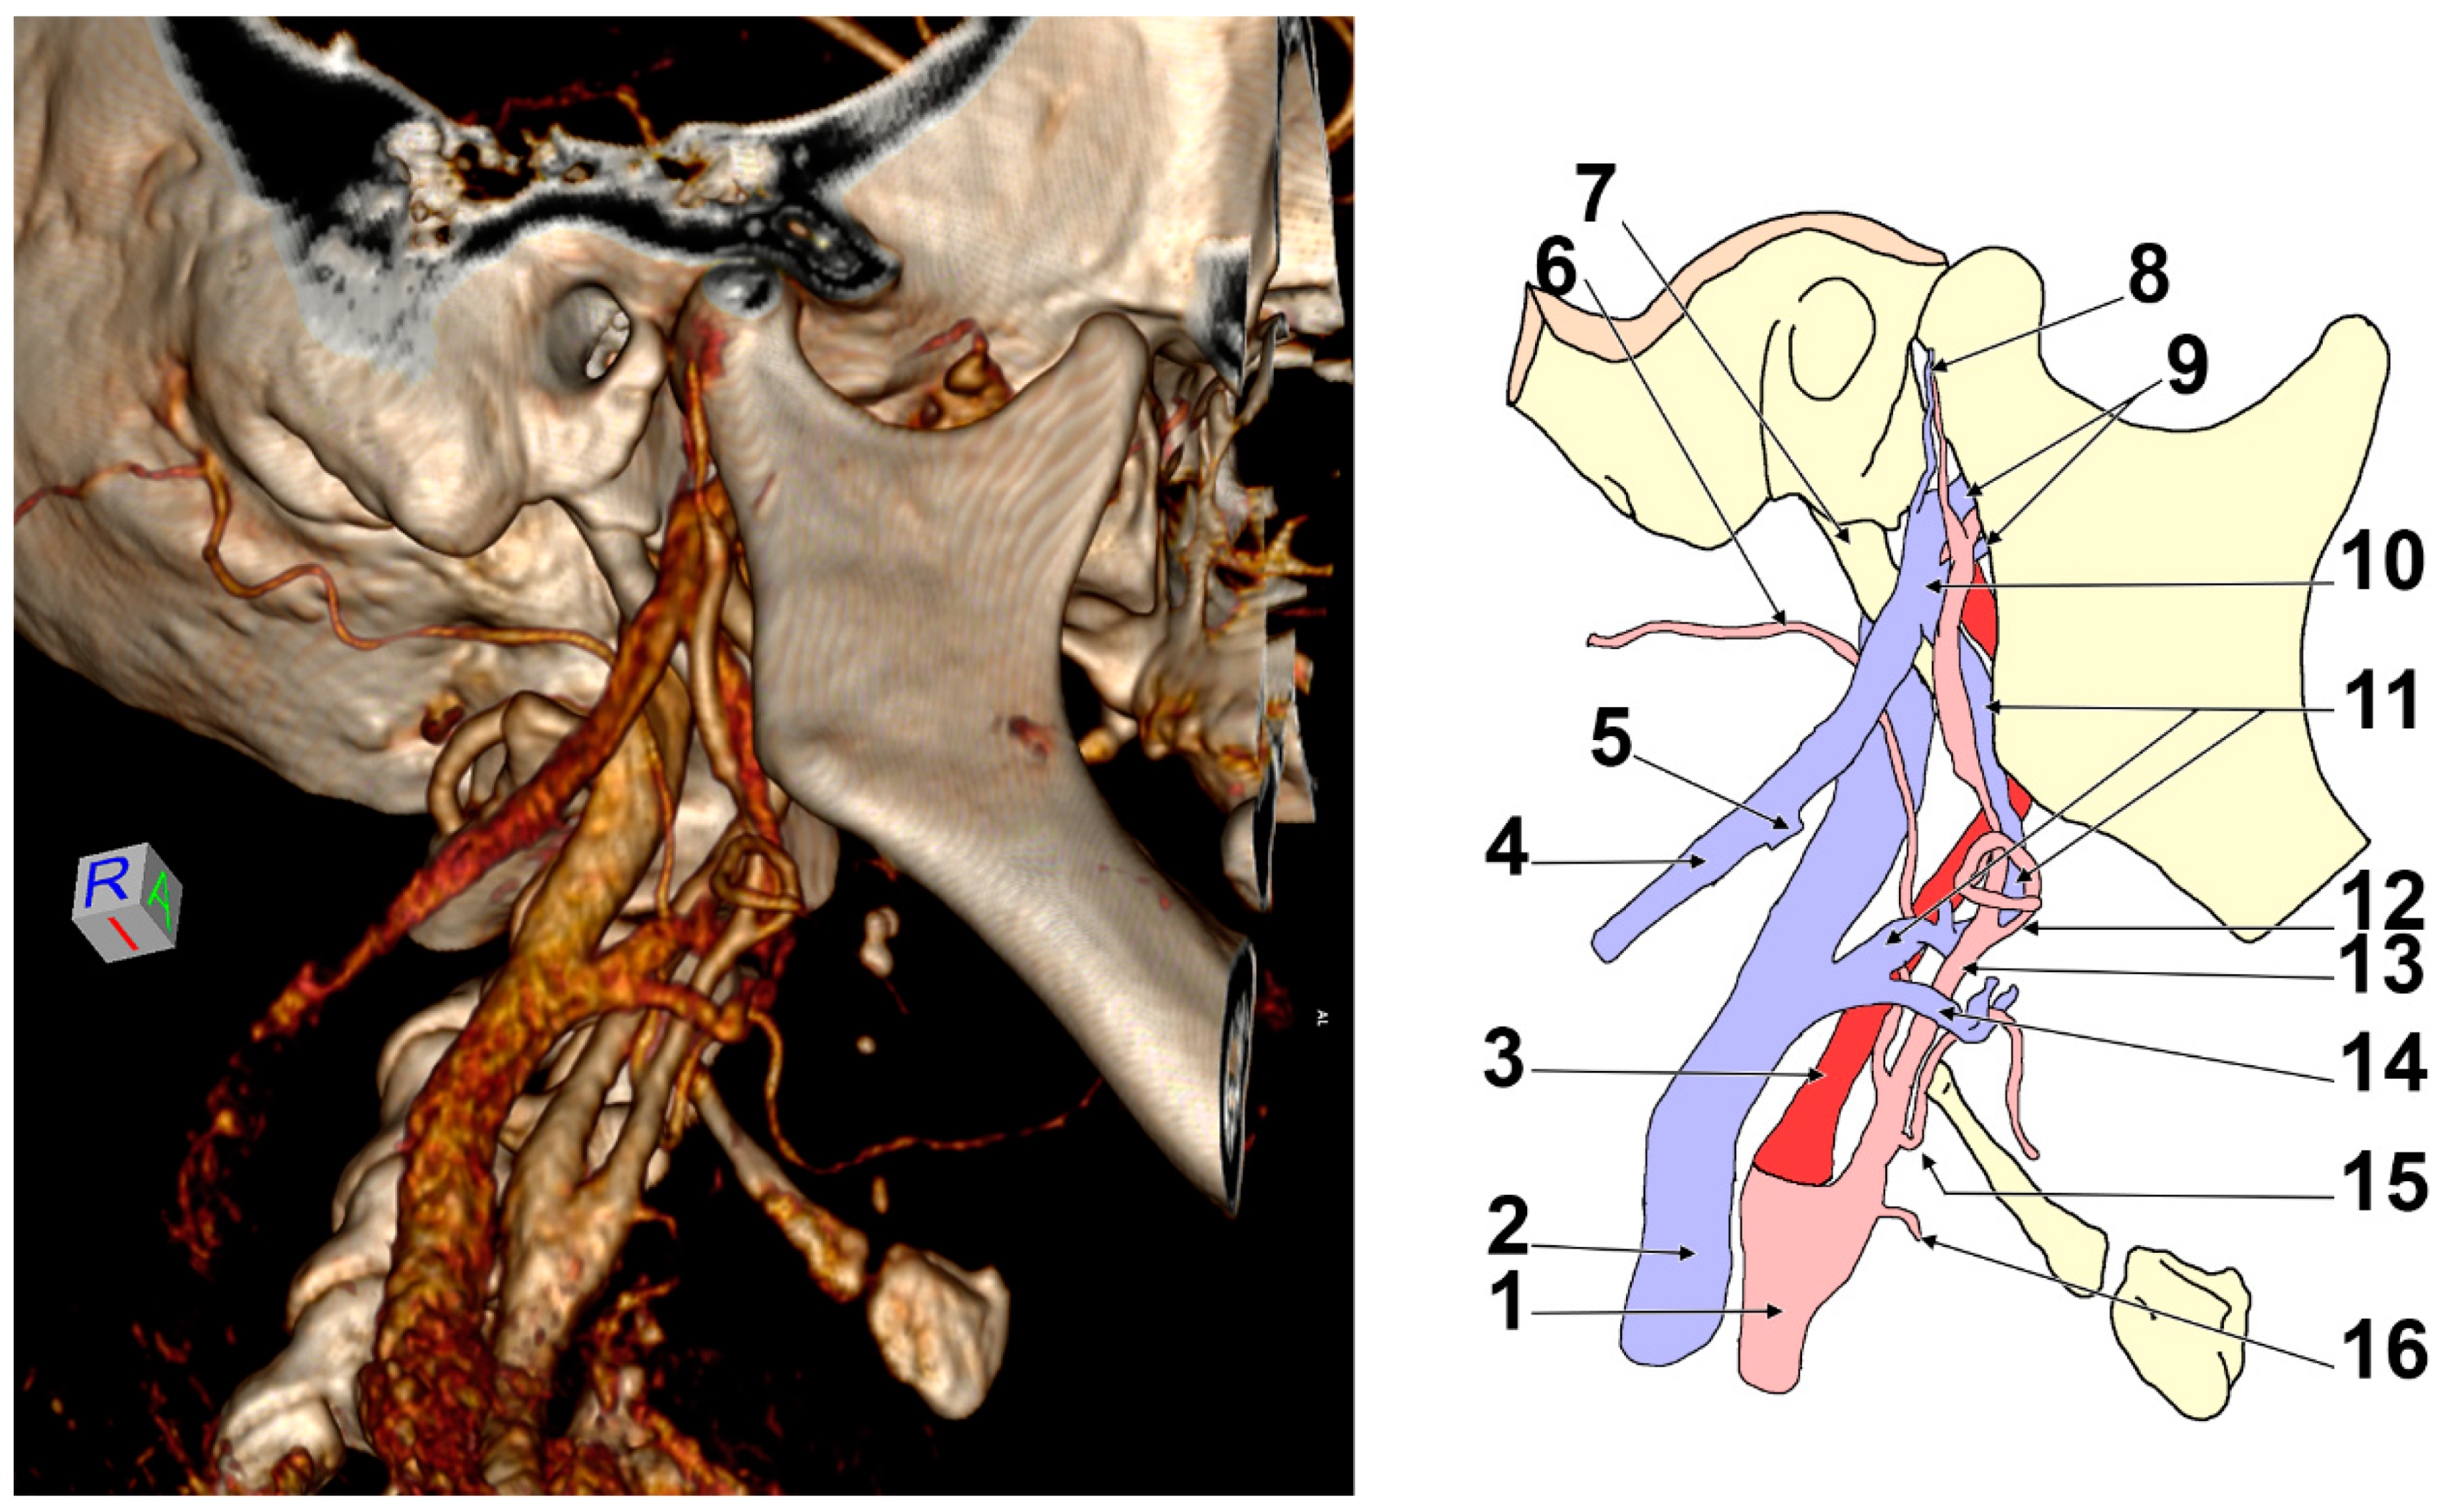

3.1. The First Variant of the ECV

3.2. The Second Variant of the ECV

3.3. The Third Variant of the ECV